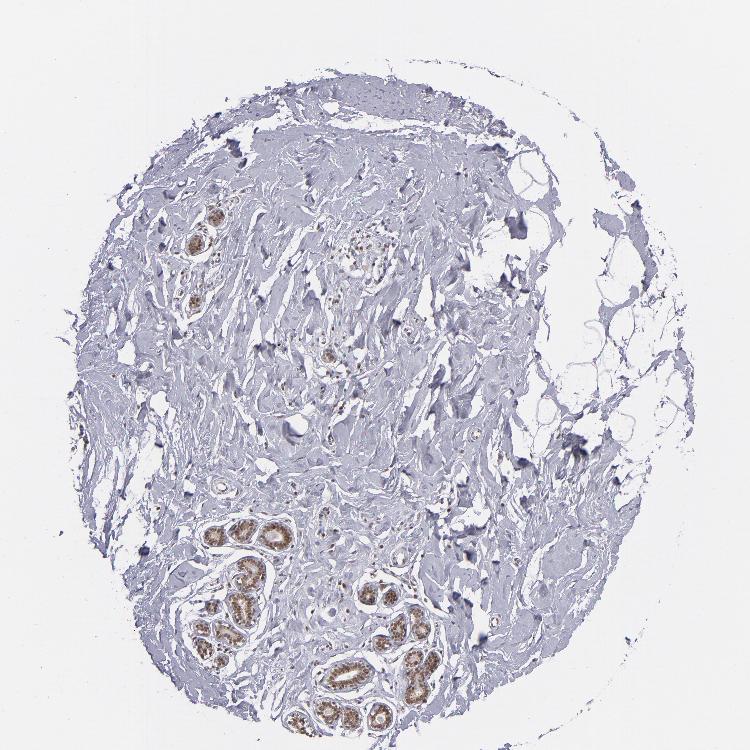

BREAST - Antibody stainingi

Antibody staining in the annotated cell types in the current human tissue is reported as not detected, low, medium, or high, based on conventional immunohistochemistry profiling in selected tissues. This score is based on the combination of the staining intensity and fraction of stained cells.

Each image is clickable and will lead to virtual microscopy that enables deeper exploration of all samples and also displays staining intensity scores, fraction scores and subcellular localization as well as patient and tissue information for each sample.

Antibody HPA001824

Adipocytes Medium

Glandular cells Medium

Myoepithelial cells Medium